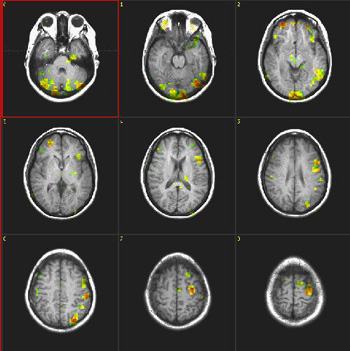

Semantic Fluency

Right handed, 25 year-old woman |

| Paradigm |

ON: Retrieving words within a given category

OFF: Think of a dark sky |

| Statistics |

| Statistical method |

P Value |

Z score |

| T-Test |

0.00005 |

4.2 |

| Activation |

The left hemisphere shows predominant activation. The following areas were activated: Broca's, left posterior portion of middle and inferior temporal gyri (Brodman's 37), left parietal and left premotor strip. Wide activation is seen in the inferior aspect of the occipital lobes. The main activation on the right is located in the inferior aspect of the frontal lobe (Brodman's 11), a finding consistently seen in this paradigm. |